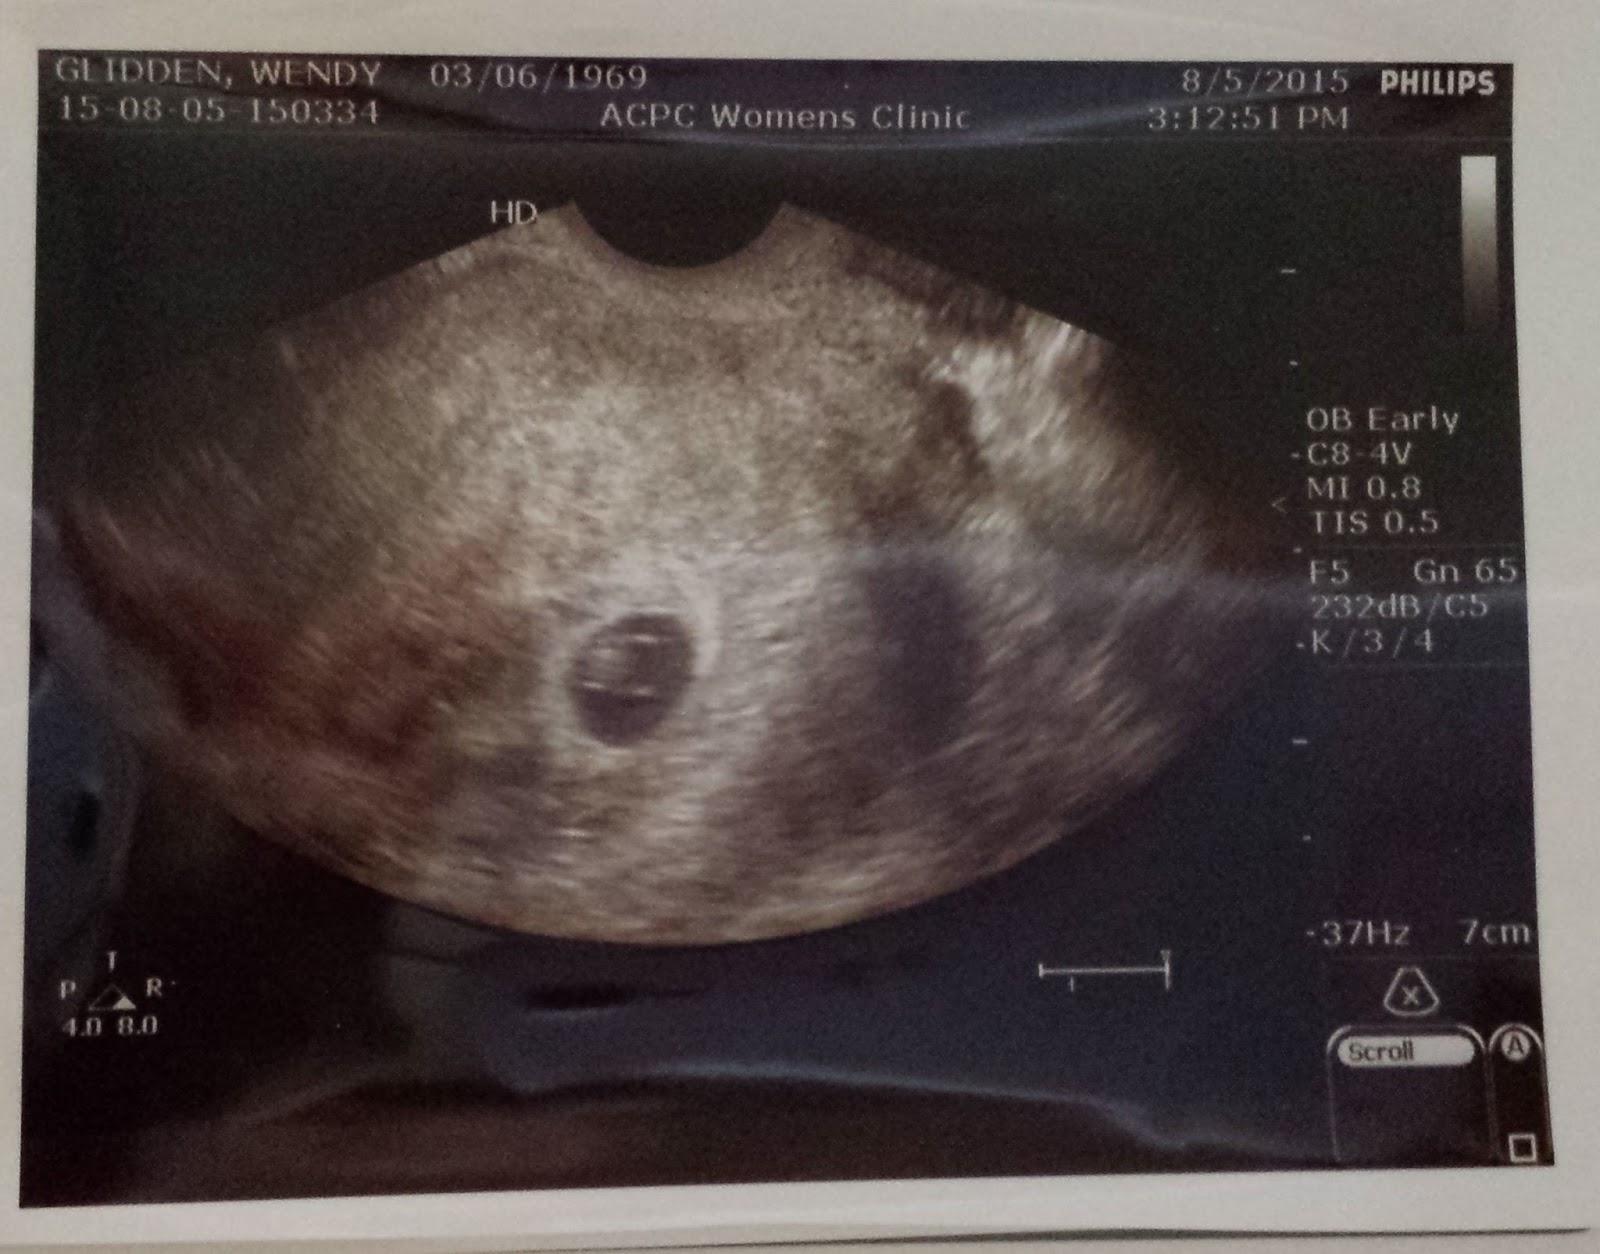

The day comes at me so fast, it often speeds by like a whirl wind! I did accomplish a lot yesterday. I picked my doctor for this pregnancy. I found a midwife! I am excited about that. I received a call from the clinic letting me know that the professional person had taken a look at my ultrasound and by all appearances I am indeed on the path to having a healthy pregnancy! That was the best news of my day!